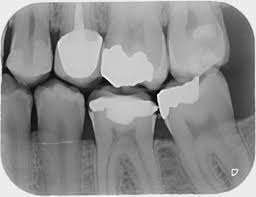

Digital X-ray

Modern technology has changed the way we take dental x-rays at Ankura Dental clinic. Advanced Digital radiology technology allows us to use computerized sensors rather than film to capture images of your teeth in order to reduce the amount of radiation exposed.